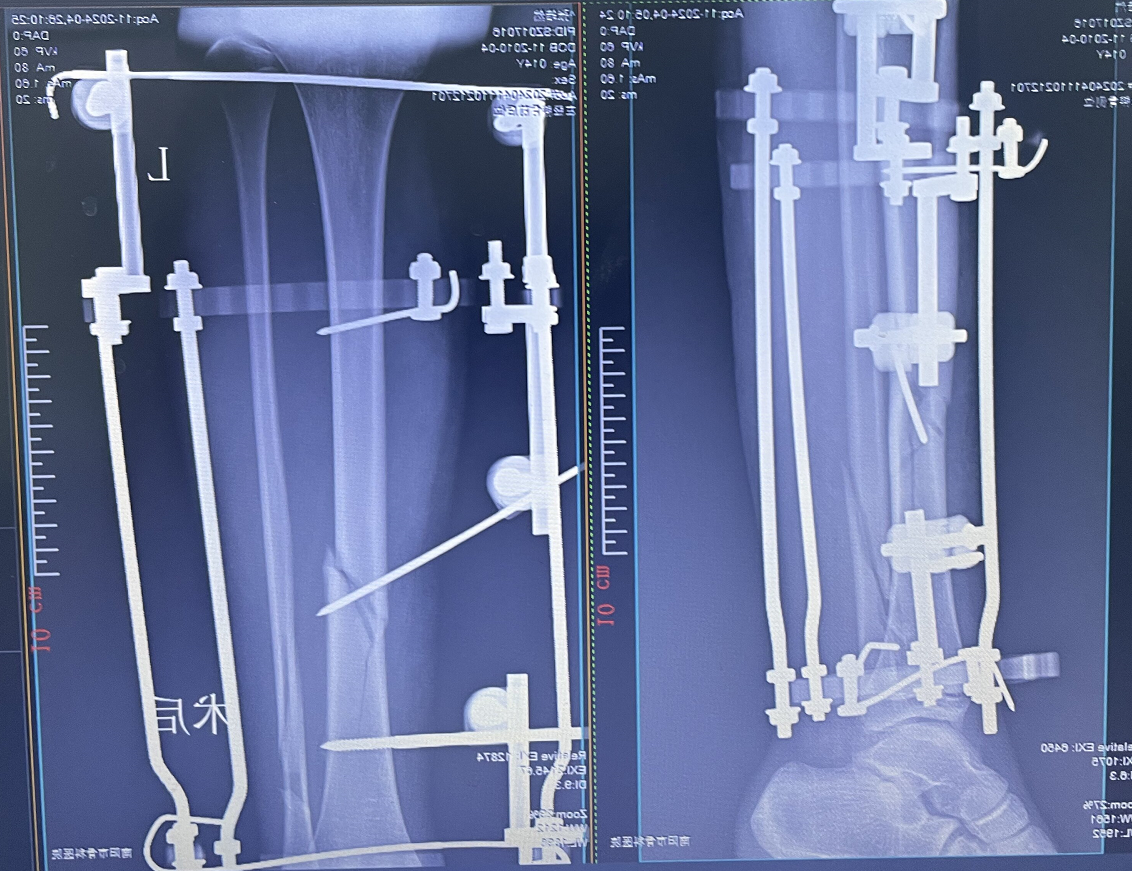

术后X片

本病例由中国中医科学院望京医院骨创伤一科提供【基本资料】患者,男,64岁术前X片···